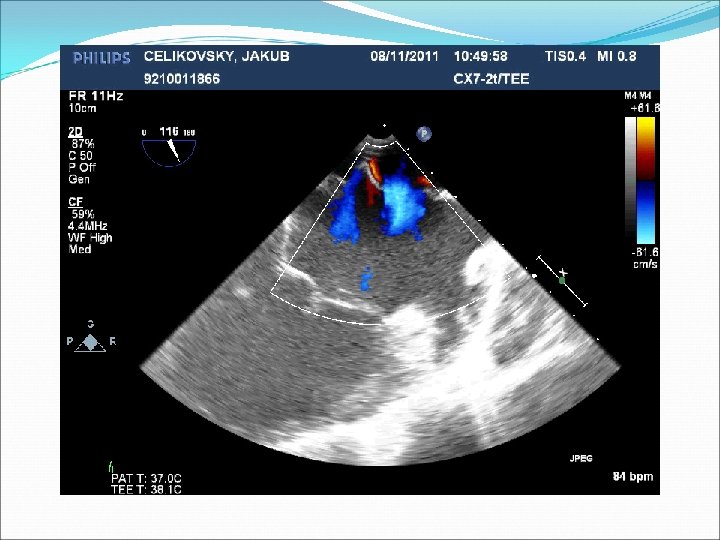

Defekt síňového septa: diagnostika echokardiografie, často jícnová: dilatovaná pravá komora zkratový proud barevným dopplerovským vyšetřením při přítomnosti trikuspidální regurgitace neinvazivně z rychlosti regurgitace odhadovat výši systolického tlaku v plicnici kalkulovat systémový průtok(Qs) ve výtokovém traktu levé komory a plicní průtok(Qp) v kmeni plicnice a počítat jejich poměr EKG: obraz bloku pravého raménka Tawarova u 95 % pacientů je projevem opožděné aktivace dilatované pravé komory Skiagram hrudníku : dilatace pravé komory, pravé síně, dilatace plicnice, zvýšenou plicní kresbu. Katetrizační vyšetření : před uzávěrem defektu u starších pacientů k posouzení plicní vaskulární rezistence a k provedení selektivní koronarografie.